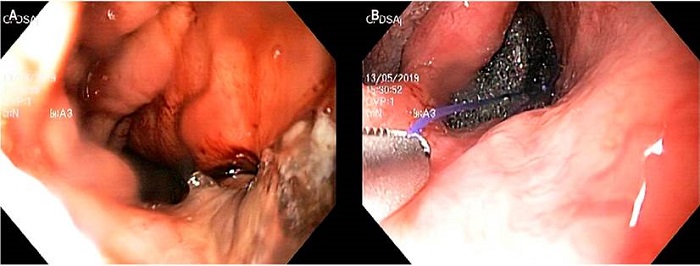

Dado la persistencia de una fístula de 5 mm sobre anastomosis se realiza terapia Endo-Vac con esponja de GranuFoamTM, conectada a un sistema de drenaje intermitente, con una presión negativa de 100 mm Hg (Figura 2). Conjuntamente se llevó a cabo una yeyunostomía laparoscópica. Se realiza recambio de esponja a los 7 días y se observa una reducción del defecto fistuloso. A las 2 semanas de inicio de la terapia se logra la adecuada cicatrización, sin evidencia de fístula. Se extrae la esponja y la sonda nasogástrica con asa de 30 mm sin complicaciones. Control endoscópico al mes y 3 meses de finalizar la terapia Endo-Vac. Anastomosis con cambios inflamatorios y disminución de la luz en 30 %, por efecto de angulación y no por estenosis, lo que permitió el paso fácil del equipo (Figura 3). Se indicó manejo con inhibidor de bomba de protones, y se logró una mejoría de la disfagia, sin dolor torácico.